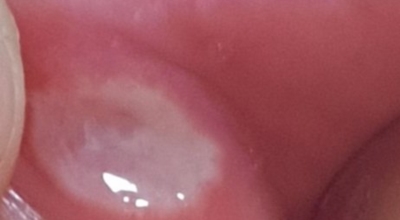

1. 구내염 원인 - 아프타성 구내염

입안 점막이 동그랗게 패여 통증을 유발한다면, 아프타성 구내염을 의심할 수 있어요. 음식을 먹을 때마다 아픈 작은 궤양이 생겼다면, 아프타성 구내염을 의심할 수 있답니다. 아프타성 구내염은 빨간색 둘레를 가진 둥근 형태의 흰색 궤양이, 얕은 깊이로 한 개 및 여러 개 생기며 통증을 동반하는 것이 특징입니다. 전 인구의 20~40%가 발병할만큼 통상적으로 나타나는 질환으로 20대, 주로 여성들에게 많이 나타나며, 일주일 정도면 자연적으로 치유되지만 1~3개월 간격으로 빈번히 재발하는 것이 특징입니다.

원인은 입 속 점막의 작은 상처나, 바이러스, 세균의 감염, 특히 수면 부족이나 과로, 스트레스가 쌓여서 면역력이 떨어졌을 때와, 비타민 B12 또는 엽산 결핍 시에 많이 생기 다고 알려져 있답니다. 흔한 질환이니만큼 자연적으로 치유 되지만, 통증을 동반하고, 궤양의 크기가 커지거나 숫자가 늘어나기도 하기 때문에 연고나 외용제, 가글액 등을 활용해서 증상을 경감시키는 치료를 하기도 해요.